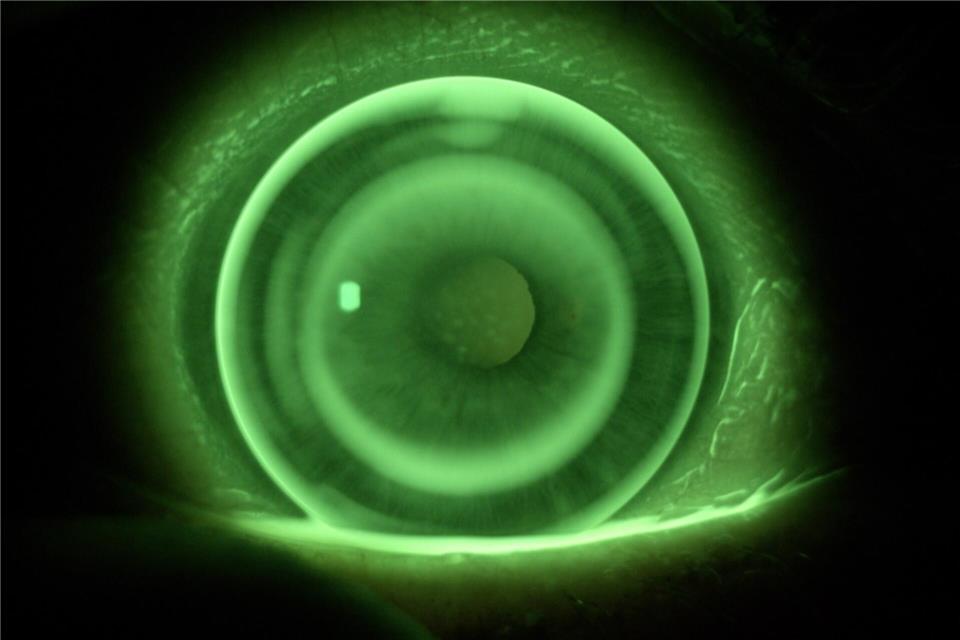

Mithilfe von Kontrastmitteln wird das Auge untersucht, um die perfekte Kontaktlinse zu finden.